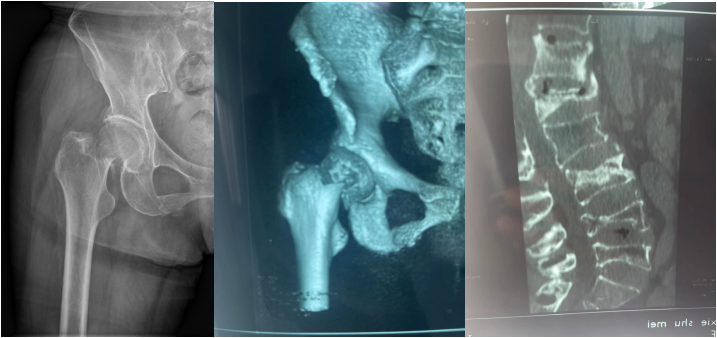

患者谢某,年过六旬,一直闲适地忙于家庭和农间琐事。然而,一场车祸使她的生活顿时陷入了慌乱。在骑车回家时,不幸被汽车撞倒,致使腰部和右髋部受伤严重,疼痛剧烈,无法...